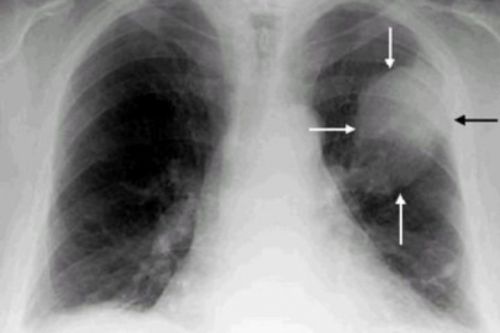

Чтобы диагностировать воспаление легких, нужна рентгенография. При подозрении на туберкулез необходимы специфические пробы на выявление возбудителя инфекции.

Диагностика в этом слечае состоит в снятии рентгенограммы, биопсии, МРТ, КТ, бронхоскопии. По результатам этих процедур назначается консервативное, хирургическое лечение.

Рентгенограмма нарушений позвоночника в результате остеохондроза

Выслушивание легочных хрипов

Четкую картину злокачественного новообразования позволяет выявить рентгенографическое исследование и биопсия (забор пораженной ткани на определение злокачественности). При необходимости назначаются МРТ, КТ, бронхоскопия и т.д. От проведенной диагностики зависит необходимый объем терапевтического или хирургического вмешательства.

Рак легкого на рентгеновском снимке